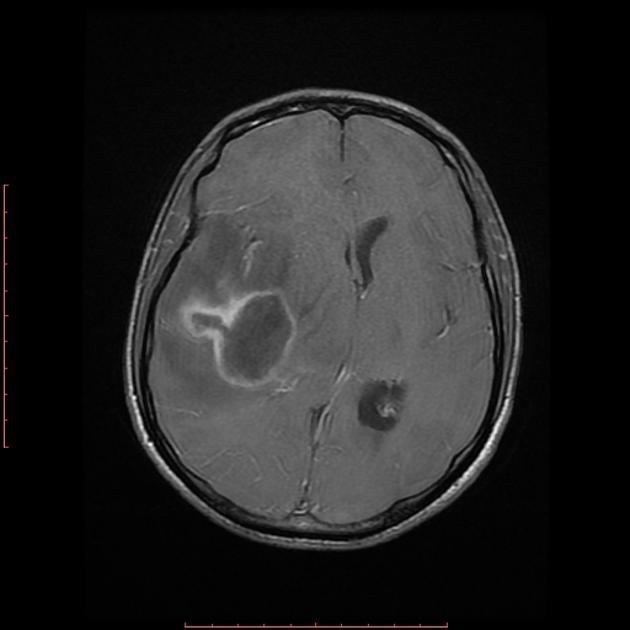

Regular follow-up care is crucial. Expect routine visits with your healthcare team. These help monitor your progress and spot any changes that might need attention. It’s important to go to all your scheduled appointments. They might include MRIs or other scans to check for any signs of the tumor’s return.